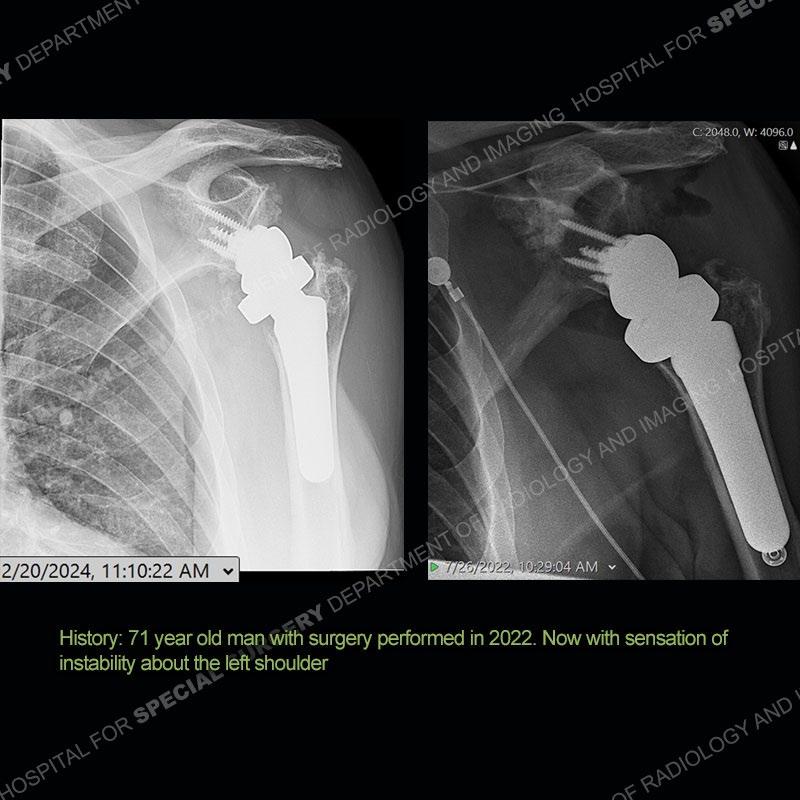

When comparing the radiographs, there is a slight change in the alignment in the components of the prosthesis. On the current radiographs, a radiolucent, crescentic focus is present at the level of the glenoid. When comparing the CT exams, there is a change at the alignment of the glenosphere and the humeral component and now a direct apposition of the components. On the current CT, the radiolucent, crescentic focus is again identified.

Diagnosis: Polyethylene Liner Dissociation

Total shoulder arthroplasty with a reverse type prosthesis is known to have certain complications such as scapular notching and acromial/scapular spine stress fractures. One of the other unique, but more infrequent complications is dissociation of the polyethylene liner from the humeral tray. Patients will present as in this case with instability and at times frank dislocation. The recognition of this process is important as it is a contraindication to attempt a closed reduction. The closed reduction will typically fail and may damage the components.

If comparison radiographs are present, subtle changes can be made more apparent. Instead of a space between the glenosphere and the humeral tray, there is a direct contact, and there may be an overall change in the alignment at the articulation. The displaced, radiolucent polyethylene liner depending on location can be seen on the radiographs, as in this case. At times, the liner may overlie other structures making identification very difficult on radiographs, but it should almost always be able to be identified on CT (as shown in this example as well). This patient is scheduled for revision procedure.